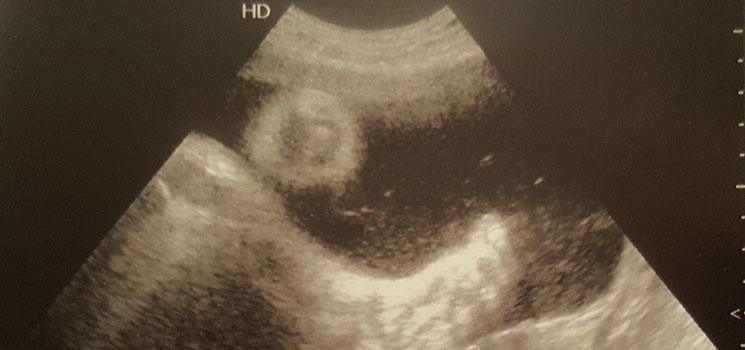

Das Wasser läuft! - Tagebücher aus der Schwangerschaft von Leandra aus Lübeck